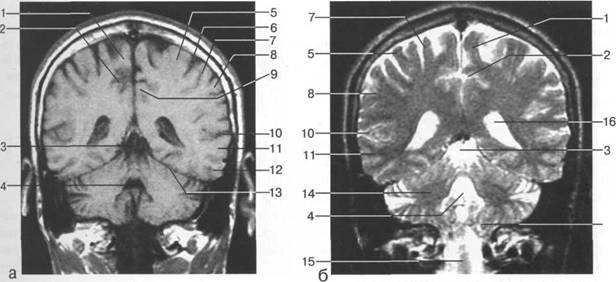

Задняя череп 13513u2010n 85;ая ямка представляет собой часть основания череп 13513u2010n 72;, ограниченную централь

Следует отметить, что в настоящее время оптимальным методом исследования структур задней череп 13513u2010n 85;ой ямки является МРТ, которая, в отличие от КТ, лишена артефактов от кост

Мозжечок заполняет практически весь объем задней череп 13513u2010n 85;ой ямки. Его поперечный раз